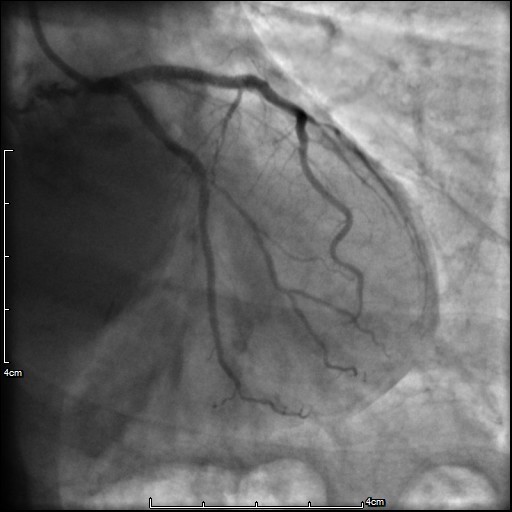

成功植入支架后复查造影